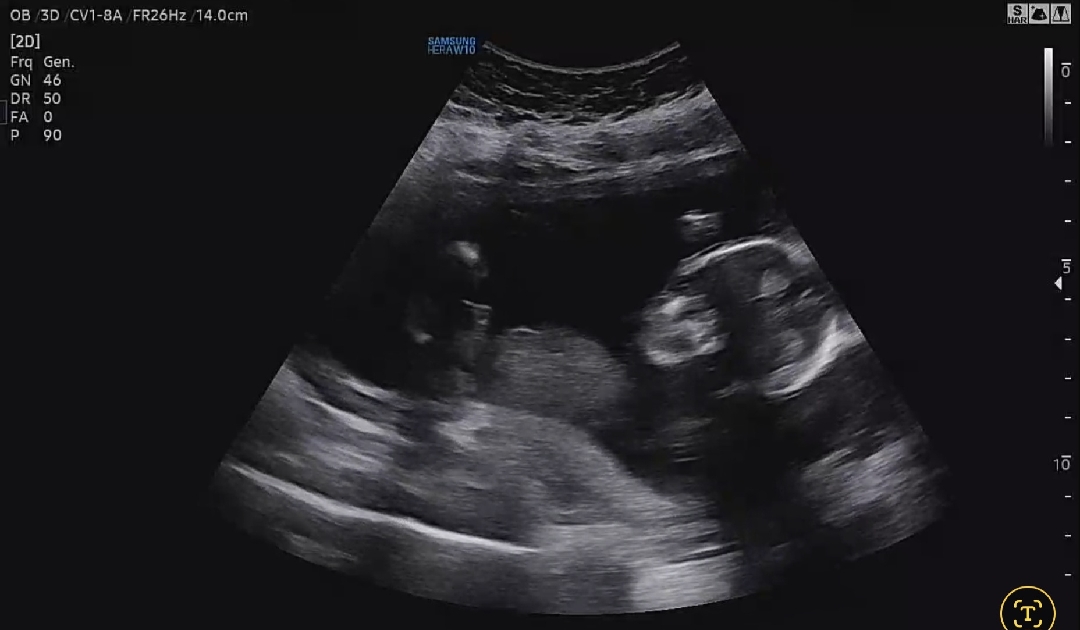

16주 성별

선생님이 아기가 잘 안보여주는데 아들인가같다고 하네요 근데 영상아무리봐도 🌶 로 보이는게 안보이고 각도법도 딸인거같은데 어때보이시나요???